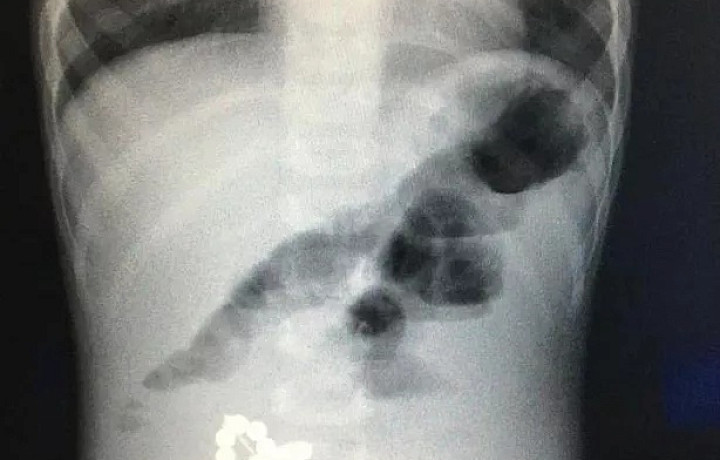

Фото: министерство здравоохранения Тульской области.

Опасные инциденты зачастую происходят неожиданно и приводят к серьезным последствиям. Ярким примером может послужить случай в январе 2025 года. В Тульской детской областной клинической больнице пришлось срочно оперировать маленького пациента, проглотившего магниты. Для того, чтобы знать, что делать в такой ситуации, в минздраве рассказали основные правила помощи.

2. Срочно необходимо обратиться к врачу. Специалист проведет обзорную рентгенографию органов брюшной полости. На снимках будут видны все рентгеноконтрастные инородные тела.